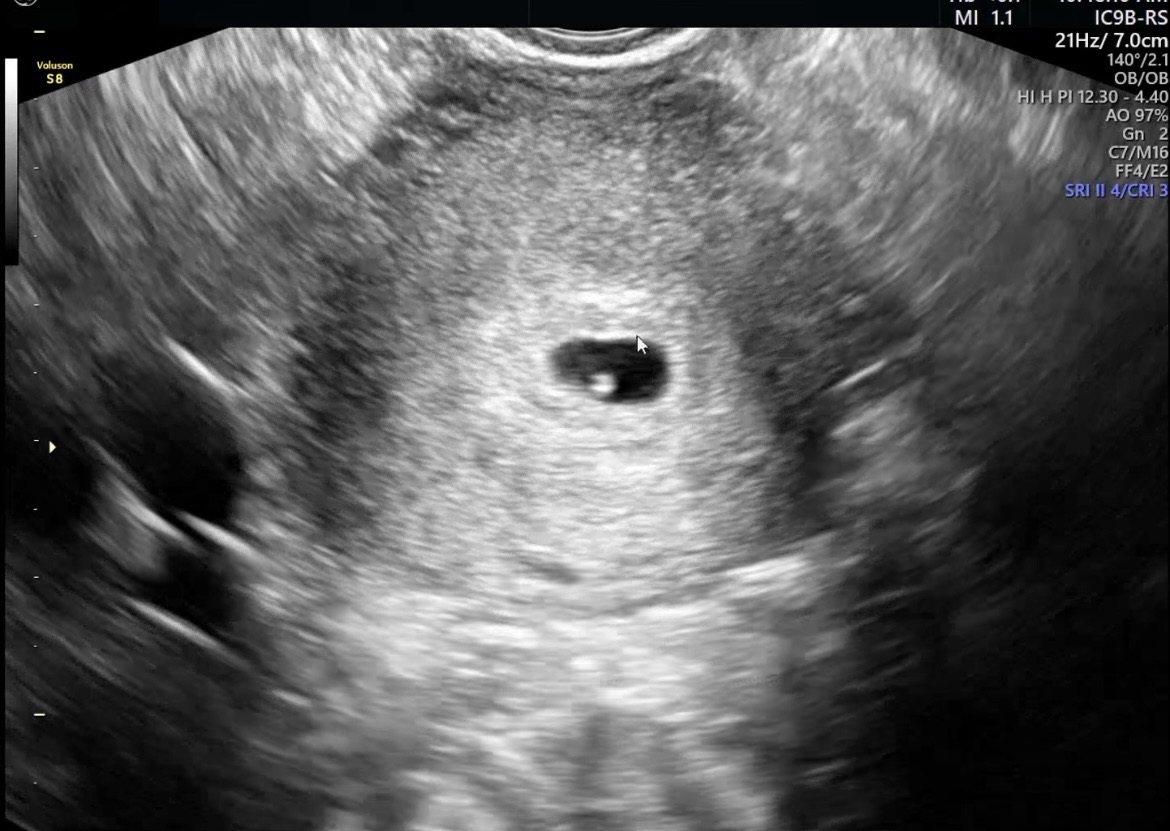

| 치료 도중 느꼈던 가장 기뻤던 순간과 절망적인 것들은 무엇인가요? 잊지 못할 경험이 있나요? | 인공수정이 반복적으로 잘 되지 않았지만, “도전하다 보면 꼭 되겠다”는 마음가짐 덕분에 절망하지 않고 치료를 이어갈 수 있었습니다. 가장 기뻤던 순간은 아이의 심장 소리를 처음 들었을 때로, 안도감과 행복감이 동시에 밀려왔던 순간이었습니다. |